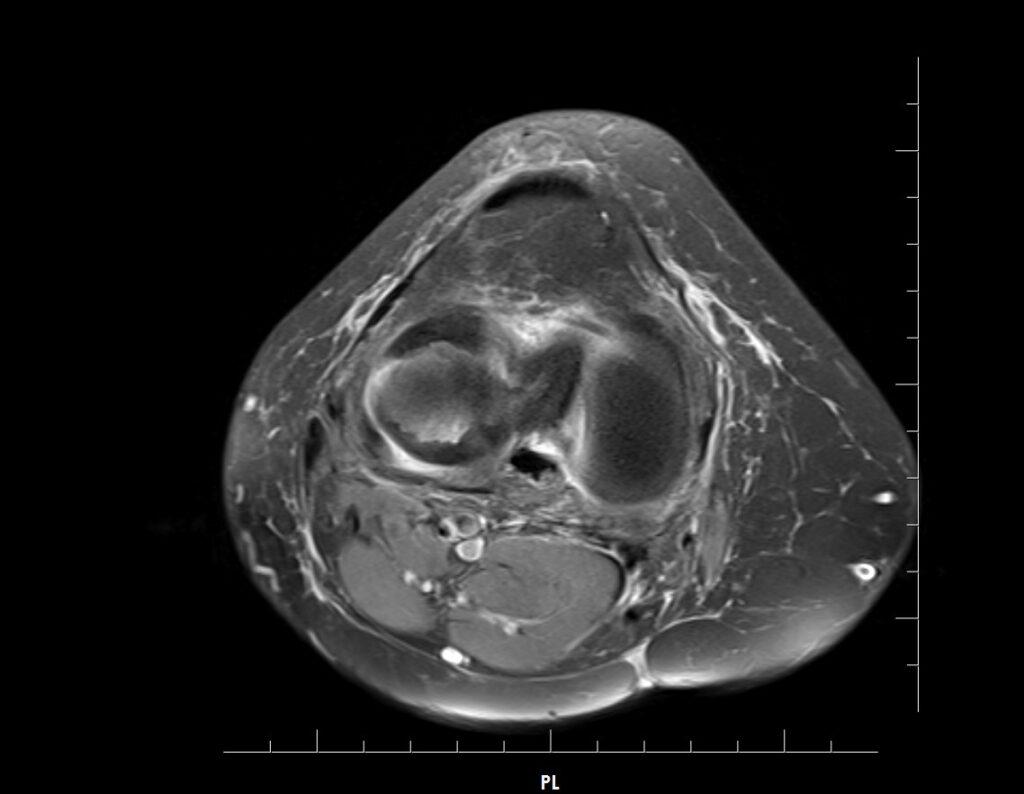

Answer: Bucket-handle tear of the lateral meniscus

Fat-suppressed images demonstrate a large displaced “handle” from the body of the lateral meniscus near the intercondylar notch.